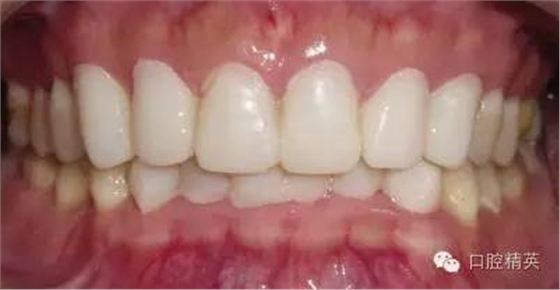

粘固后,對(duì)咬合關(guān)系進(jìn)行初步調(diào)整。三天后,復(fù)查,進(jìn)一步確認(rèn)咬合關(guān)系,必要時(shí)進(jìn)行調(diào)整(見(jiàn)圖12)。

LAVA 全瓷冠強(qiáng)度高,顏色自然,邊緣高度密合,切端可見(jiàn)半透明感,整體效果理想,與修復(fù)前(見(jiàn)圖1)相比取得了醫(yī)患均滿意的效果。